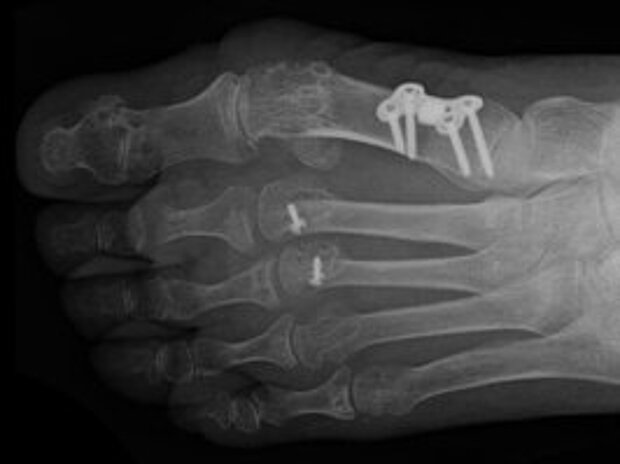

- Hallux valgus (Schiefstellung der Großzehe im Grundgelenk): Behandlung durch Chevron-, Scarf-, Ludlof-Osteotomie, Lapidus-Operation

- Cheilektomie, Grundgelenksprothese Zeh 1

Zum Einsatz kommen moderne operative Behandlungsmethoden und Osteosyntheseverfahren. Implantiert werden Stahl- und Titanmaterialien: Schrauben, Platten, winkelstabile Platten, kanülierte Schrauben, Kirschner-Drähte, Kleinfragmentplatten und externe Fixateure.